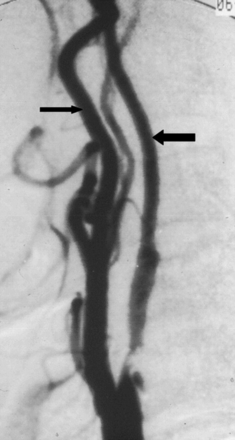

A case with near-occlusion with full collapse, reprinted with permission from Fox et al.1 Lateral common carotid angiogram shows the thin, threadlike, collapsed lumen (arrows) of the ICA above a prominent ICA stenosis at the bulb (not shown).